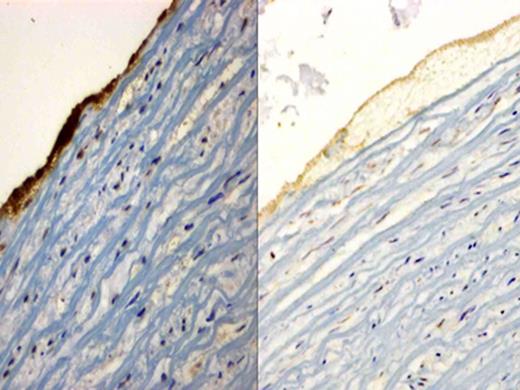

Immunohistochemical staining of glycoprotein IIb/IIIa receptor, sections were incubated with the mouse anti-human integrin alpha-2b/beta-3 monoclonal antibody and counterstained with hematoxylin. The image on the left is the representative image of thrombus caused by Thrombosomes in PFP. It shows an intense dark stain suggestive of glycoprotein IIb/IIIa receptor expression. The image on the right is PFP and only shows background staining, confirming absence of glycoprotein IIb/IIIa receptor expression.

Thrombosomes contributed towards thrombus formation in whole human blood as evidenced by incorporation of fluorescent-labeled Thrombosomes into the thrombus. Immunohistochemical staining of the glycoprotein IIb/IIIa receptor confirmed incorporation of Thrombosomes into the thrombus. In the high shear chamber, mean thrombus area increased in a dose-dependent manner following the addition of Thrombosomes (704 μm2 [95% CI, 224 – 1184 μm2], 1511 μm2 [95% CI, 687 – 2336 μm2] and 2378 μm2 [95% CI, 1567 – 3189 μm2] for PFP and Thrombosomes at concentrations of 20 and 200 × 106/mL respectively [P= 0.003]). In the low shear chamber, total thrombus area for the PFP was 4962 μm2 (95% CI, 2489 – 7434 μm2). The addition of Thrombosomes at concentrations of 20 and 200 × 106/mL led to a numerical increase in mean thrombus area to 6170 μm2 (95% CI, 3944 – 8397 μm2) and 7504 μm2 (95% CI, 3864 – 11144 μm2) respectively, although this was not statistically significant (P= 0.2969).